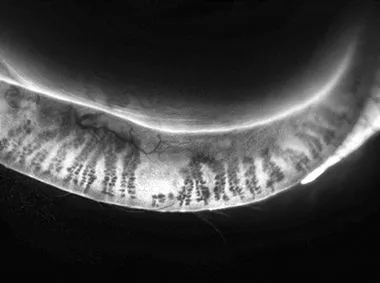

Dynamic Meibomian Imaging

MEIBOMIAN GLANDS IN HIGH DEFINITION1

Dynamic Illumination

Surface lighting originates from multiple light sources to minimize reflection.

Adaptive Transillumination

Changes to the light intensity across the surface of the illuminator compensate for the lid thickness variations between patients.

Dual-Mode DMI

Dynamic Illumination offers an enhanced view of meibomian gland structure.

Dynamic Meibomian Gland Imaging

Utilizes advanced illumination technology to capture high-definition images.